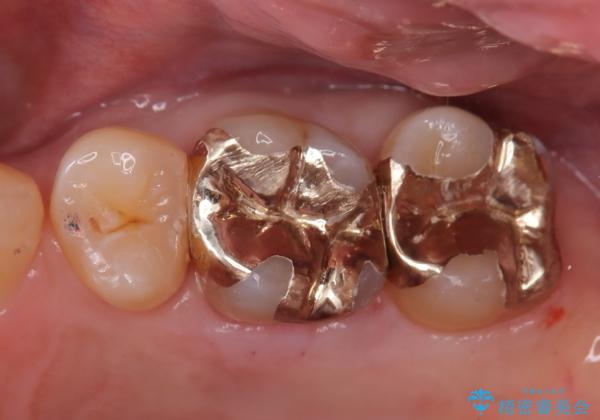

ゴールドインレーの場合、歯質とのすり合いを行い適合性を高めています。

PGA(ゴールド)クラウン、インレーの注意事項(リスク・副作用など)

- インレーおよびクラウンは脱離するリスクがあります

- 形成量はセラミックより少ないですが、歯の形成、修復後に歯に症状が出ることがあります